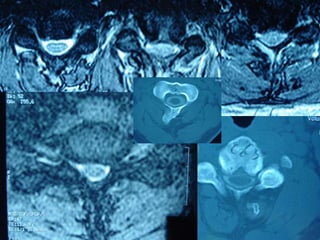

47 year old woman with 6 month h/o neck stiffness and pain with

left UE paresthesias into

The elbow forearm and hand especially IF/thumb

47 year oldwoman with 6 month h/o neck stiffness and pain with left UE paresthesias into The elbow forearm and hand especially IF/thumb